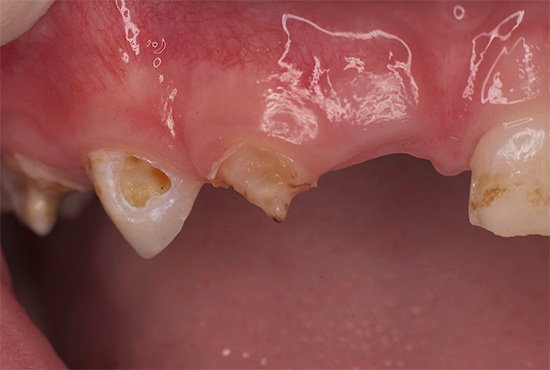

Nella foto sotto - tipica carie di bottiglie in una fase avanzata di sviluppo. In alcuni punti, lo smalto dei denti è completamente collassato e sono visibili lesioni profonde della dentina, che si scuriscono rapidamente a causa della pigmentazione di vari coloranti alimentari e prodotti di scarto di batteri:

Nelle prime fasi, la carie di bottiglia può manifestarsi sotto forma di punti chiari opachi (stadio di una macchia bianca o di gesso), che nel tempo assumono la forma di rugosità sullo smalto, gradualmente si approfondiscono e si scuriscono.

Di norma, la carie di bottiglia colpisce prima i quattro denti superiori anteriori del bambino. Il processo cariato spesso inizia nella zona gengivale, copre rapidamente l'intero dente attorno alla gengiva lungo il perimetro e penetra negli strati profondi di smalto. Il danno alla zona gengivale del dente è una caratteristica della carie in bottiglia.